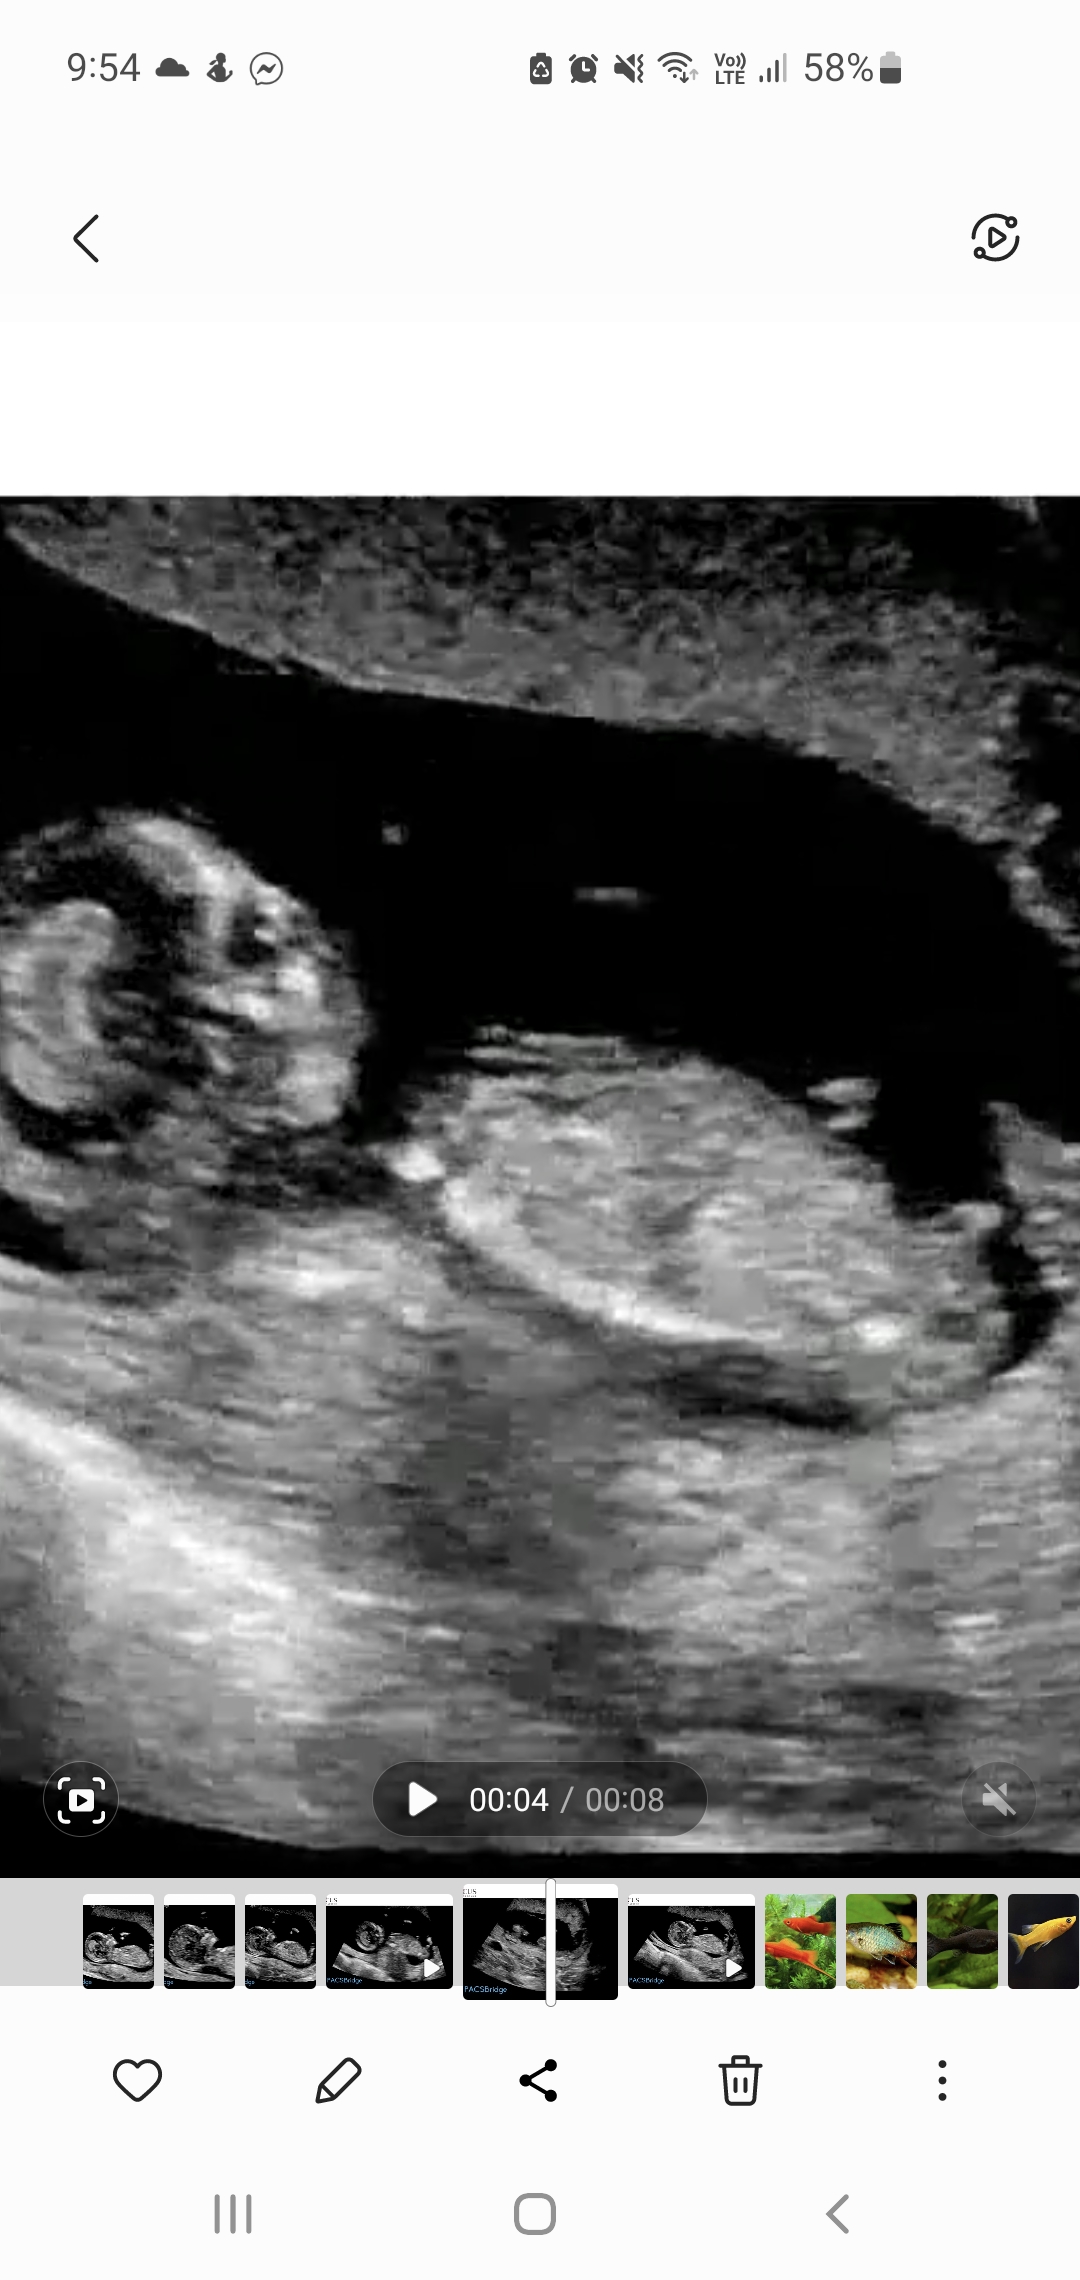

5th baby nub opinions please! 13th week

I swayed pink for a sister for my dd so I'll be honest I'm looking for hope this is a girl. So far only had boy comments elsewhere although some of the mods are 'maybe' boy, not 99%.

Atomic you've seen one of my pics in my swaying thread already but these are some more I've got from pausing the video (every micro second!). Baby was not in perfect sagittal position. I did during the scan see flashes of a long white, flat nub but she didn't capture it. She was trying to image the legs for nicer pics!

The skull/face reminds me of DDs scans but I've dreamt this bub is a boy which also happened just before I found out DS3 was a boy.

Gestation is 12+6 by OPKs & BBT, 13+5 by CRL.Attachment 43684Attachment 43685Attachment 43686Attachment 43687Attachment 43688